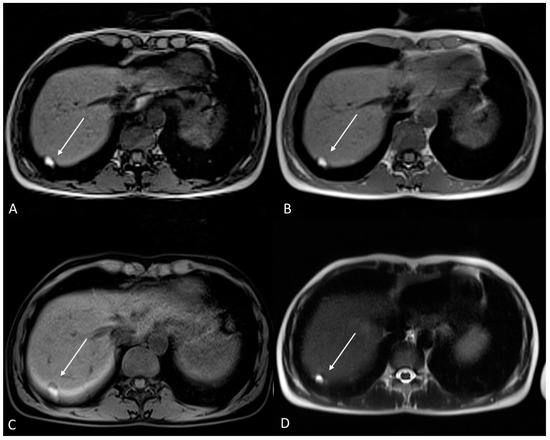

Figure 7.

Ovarian endometrioma in a 37-year-old female. (A) Axial T1WI; (B) Axial fat-suppressed T1WI. Typical aspect of an ovarian endometrioma (white arrows).

Figure 8.

Right tubo-ovarian endometriosis in a 25-year-old female patient with reported localized abdominal pain in the right iliac fossa, which increases intensity during the menstrual cycle. (A) Axial T2WI; (B) Axial fat-suppressed T1WI. Enlarged right adnexal cyst with incomplete septa denoting dilated tube (white arrows). The cystic content shows low signal intensity on T2WI and high signal intensity on fat-suppressed T1WI, consistent with hemorrhagic fluid.